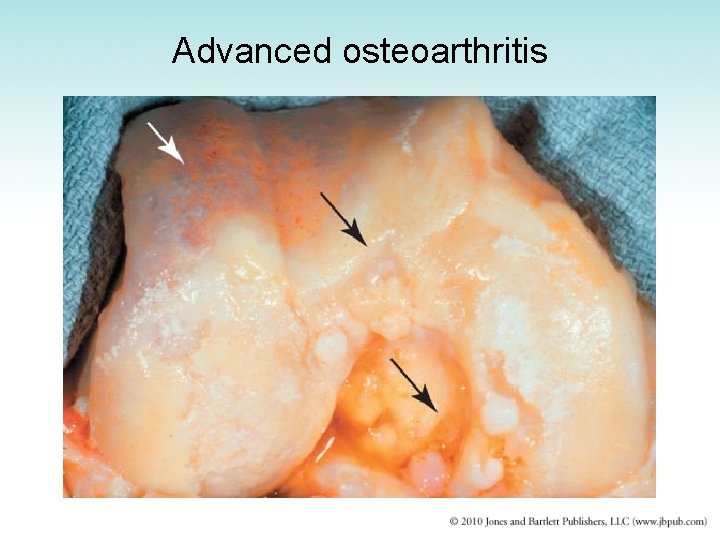

Advanced osteoarthritis